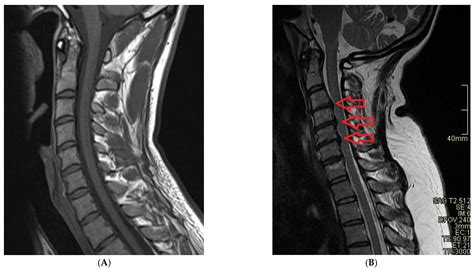

• Neurological Imaging: It is used to detect brain tumors, strokes, and other neurological conditions. The detailed images help neurologists identify abnormalities and plan treatment strategies.

Spinal Disorders Evaluates the spine for herniated discs, spinal stenosis, and other conditions affecting the spinal cord and nerves.